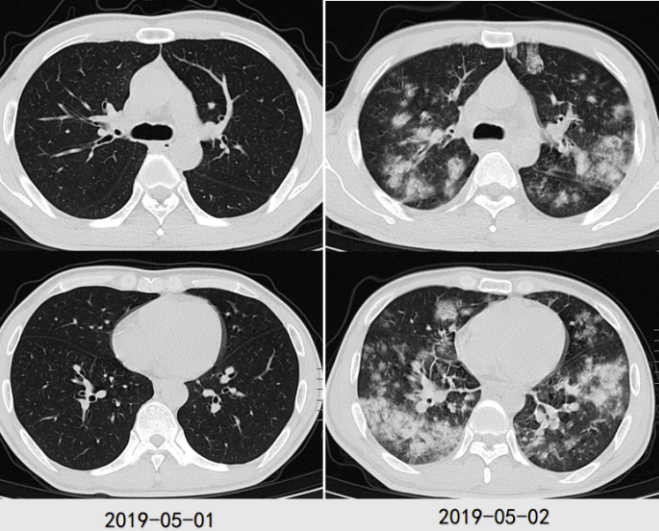

病例1:38岁男性患者,有2型糖尿病基础病史,以"高热、咳嗽4天,呼吸困难1天"为主要表现,呈急性病程。患者病情进展极快,短时间内即出现呼吸衰竭、脓毒性休克等严重并发症。影像学检查显示,2019年5月1日胸部CT未见明显异常,仅1天后(5月2日)复查,胸部CT已出现两肺弥漫性渗出改变。最终病原学检查确诊为耐甲氧西林金黄色葡萄球菌(Methicillin-Resistant Staphylococcus Aureus, MRSA)感染。

图2 病例1胸部CT变化